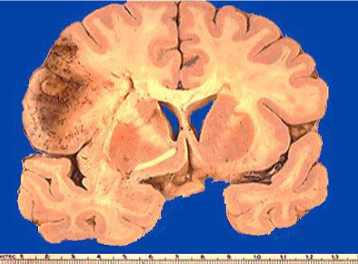

term image

White anemic infarct

Cerebral infarct